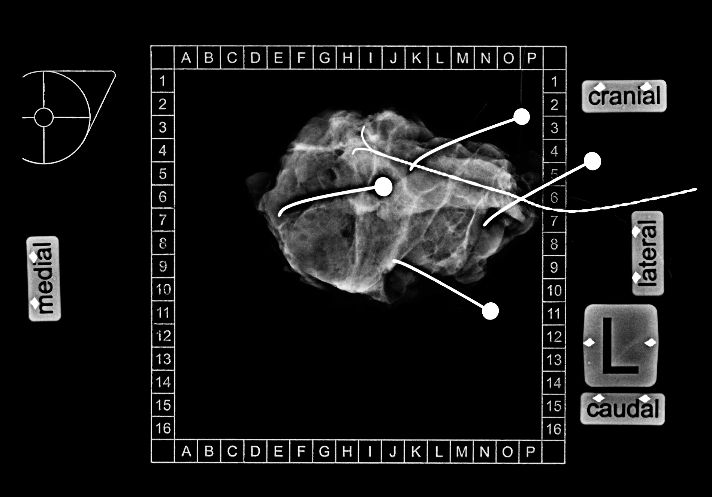

Präparateradiographie Die Präparateradiographie soll sicherstellen, dass der Befund vollständig entfernt wurde. Spezielle Aufnahmesysteme erlauben die exakte geometrische Zuordnung der Schnittränder.

71-jährige Frau mit Hypertonus und Kardiomyopathie. Vor 10 Tagen brusterhaltende Operation eines 23mm großen Mammakarzinoms rechts oben außen.